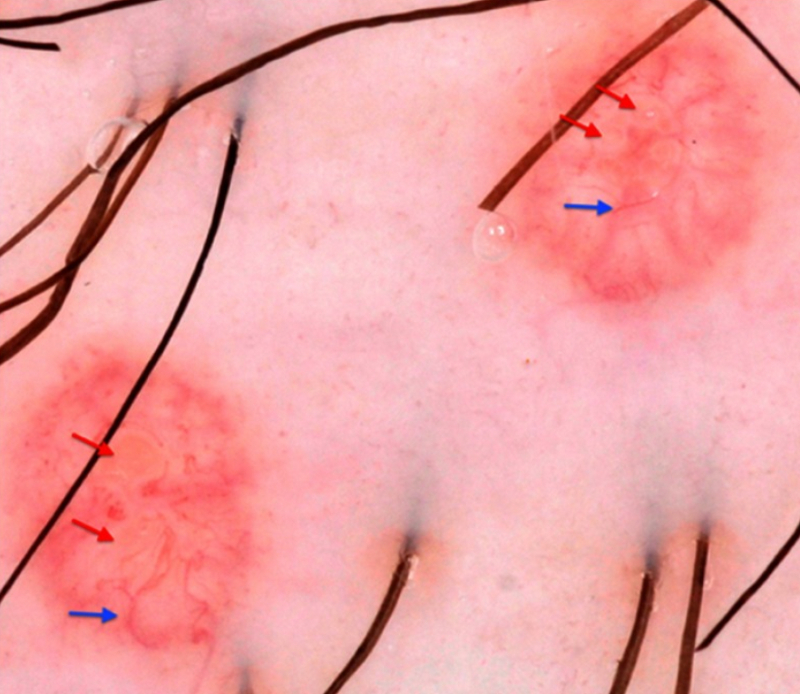

Dermoscopy may facilitate diagnosis by revealing a central, poly-lobular, white-yellow, structureless area, surrounded by vessels in a crown pattern.[13][Figure caption and citation for the preceding image starts]: Dermatoscopic findings of Molluscum contagiosum. Red arrows indicate white-to-yellow polylobular structures; blue arrows: crown vessels. (Polarised-light dermoscopy, original magnification 10x)Clinical, Cosmetic and Investigational Dermatology 2019:12 373-381. Originally published by and used with permission from Dove Medical Press Ltd. [Citation ends].